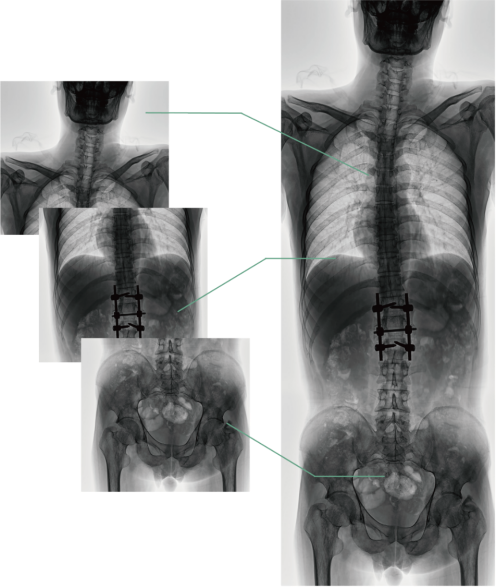

四、圖像自動(dòng)拼接

圖像自動(dòng)拼接功能實(shí)現(xiàn)全脊柱、全下肢全景攝影,解決在觀察頸椎至尾椎的脊柱側(cè)彎或其他病變時(shí)不能一次成像的問(wèn)題,能夠直觀的顯示脊柱和下肢的整體解剖形態(tài)及側(cè)凸部位。